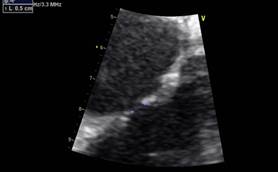

La distancia del defecto al plano valvular tricúspideo (borde anteroinferior) es de 11 mm. (Figura 5 )